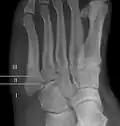

- Proximal diaphysis, typically stress fracture.[12][13]

- Metaphysis: Jones fracture[14]

-Tuberosity: Pseudo-Jones fracture[15] (avulsion fracture).[15]

Normal anatomy:

- Apophysis: Normal at 10 - 16 years.[16]

- Os vesalianum, an accessory bone.[17]

Other proximal fifth metatarsal fractures exist, although they are not as problematic as a Jones fracture. If the fracture enters the intermetatarsal joint, it is a Jones fracture. If, however, it enters the tarsometatarsal joint, then it is likely an avulsion fracture caused by pull from the fibularis brevis tendon. An avulsion fracture at the base of the fifth metatarsal is sometimes called a "dancer's fracture" or a "pseudo Jones fracture", and usually responds readily to non-operative treatment.[18] The X-ray appearance of the developmental "apophysis" in this area may have some resemblance of a fracture, but is not a fracture; it is the secondary ossification center of the metatarsal bone. It is a normal finding that occurs at this site in adolescents.[19] If an injury to that area has occurred, the physician is often able to interpret certain radiographic clues to make the differentiation. An avulsion fracture at this location is typically extra-articular and oriented transversally as compared to the longitudinal orientation of an unfused apophysis.[19]

Zones I and III have been associated with relatively guaranteed union and this union has taken place with only limited restriction of activity combined with early immobilization. On the other hand, zone II has been associated with either delayed or non-union and, consequently, it has been generally agreed that fractures in this area should be considered for some form of internal immobilization, such as internal screw fixation.

These zones can be identified anatomically and on x-ray adding to the clinical usefulness of this classification.[21] Surgical intervention is not, by itself, a guarantee of cure and has its own complication rate. Other reviews of the literature have concluded that conservative, non-operative, treatment is an acceptable option for the non-athlete.[22]

-

Anatomy of the fifth metatarsal. -

3 zone description -

2 zone description